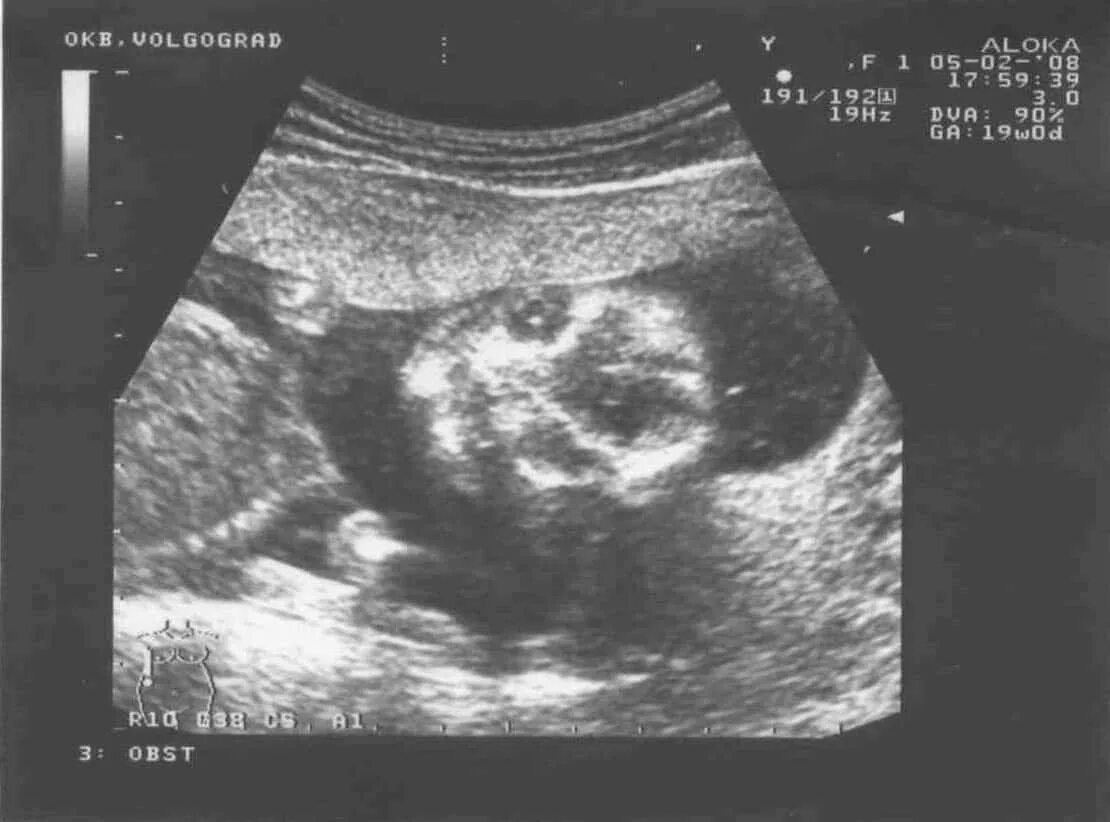

18 недель как выглядит малыш